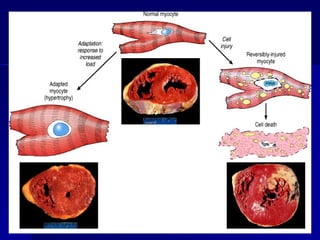

ADAPTACIÓN CELULAR

ESTRESS

Demanda

funcional

aumentada

Lesión

Celular

reversible

ADAPTACIÓN

Estrés persistente

HIPERTROFIA

- Aumento del tamaño de un órgano o tejido por

aumento del tamaño celular y aumento de su

función.

- Aumento de componentes celulares y estructurales.

- El Útero es receptor estrogénico en el músculo liso:

proteína y ADN: hipertrofia fisiológica.

- Músculo estriado y cardiaco: mayor capacidad de

hipertrofia.

- Aumento de síntesis de proteínas y miofilamentos.

- Demanda funcional aumentada. Músculos,

hipertrofía cardiaca por hipertensión, hepatocitos

(aumento de REL por estímulo de fenobarbital y

drogas hipolipemiantes)- hepatomegalia fisiológica

- Hipertrofia del riñón contralateral.

- Más frecuentes en tejidos pemanentes y

estables.